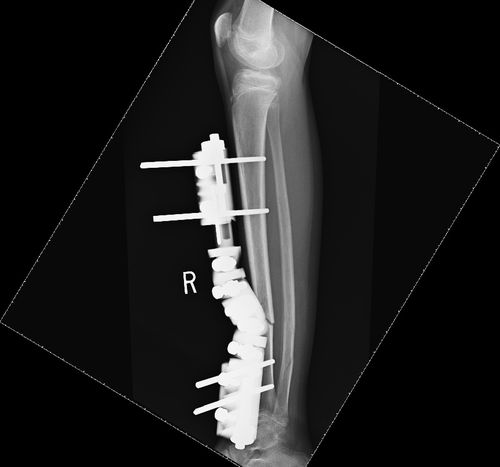

This 12-year-old presented with a short oblique fracture to the right tibia and a segmental fracture to the fibula. Attempts at closed manipulation were unsuccessful.

He therefore had external fixation applied.